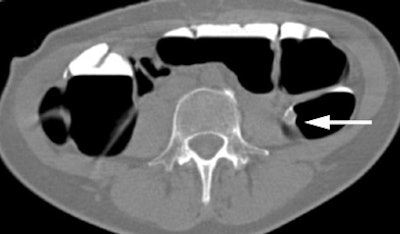

| Sagittal VC image confirms the presence of the polyp (arrow) within the descending colon. Image courtesy of Dr. Riccardo Iannaccone. |

Results from the first 130 patients showed that the positive predictive value was 79.3% and the negative predictive value (NPV) was 96%, Iannaccone said in his RSNA presentation. "This is a very important result, because NPV represents the ability of CTC to identify patients without colorectal polyps," he said.